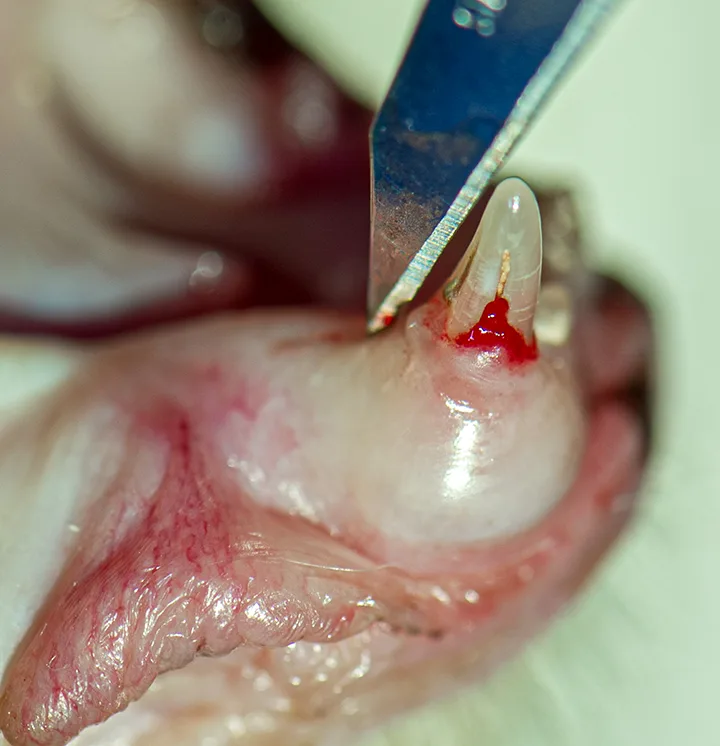

Use a #11 scalpel blade to make a caudal incision in the gingiva for flap exposure of the coronal root.

Author Insight

For premolars and molars, either an envelope flap or 1 to 2 vertical and sulcular incisions should be made to expose the root.